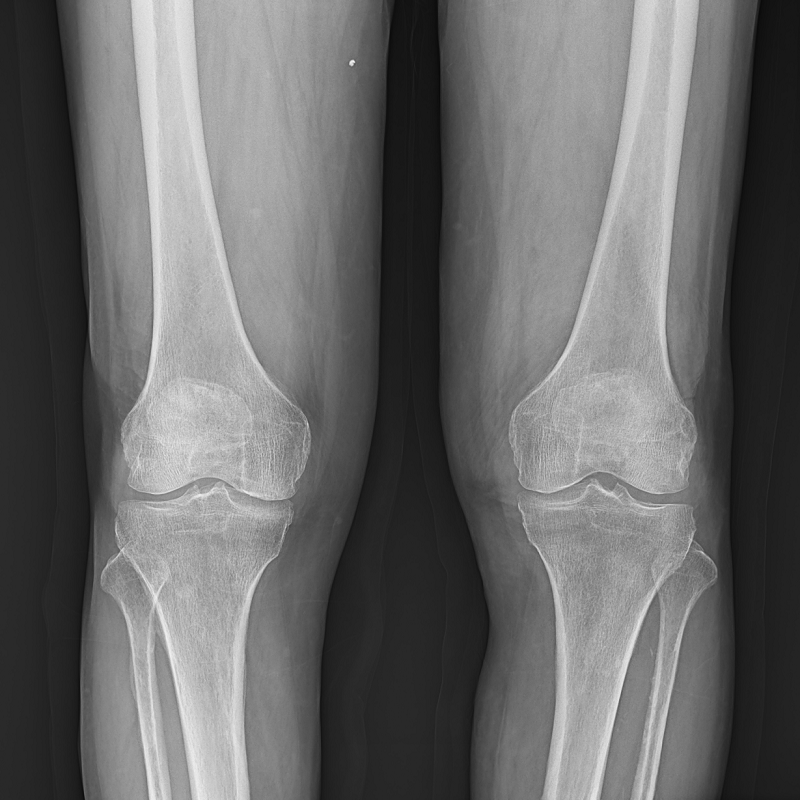

●呈現(xiàn)全下肢或全脊柱圖像

●在脊柱及下肢畸形矯正手術(shù)治療中,為術(shù)前方案制定和術(shù)后復(fù)查提供精準(zhǔn)測(cè)量

●有效解決傳統(tǒng)X光片不能一次成像問題,為患者提供更加優(yōu)質(zhì)的醫(yī)療服務(wù)

點(diǎn)片裝置可實(shí)現(xiàn)大范圍縱向移動(dòng),高效完成各部位、全身拼接等檢查需求